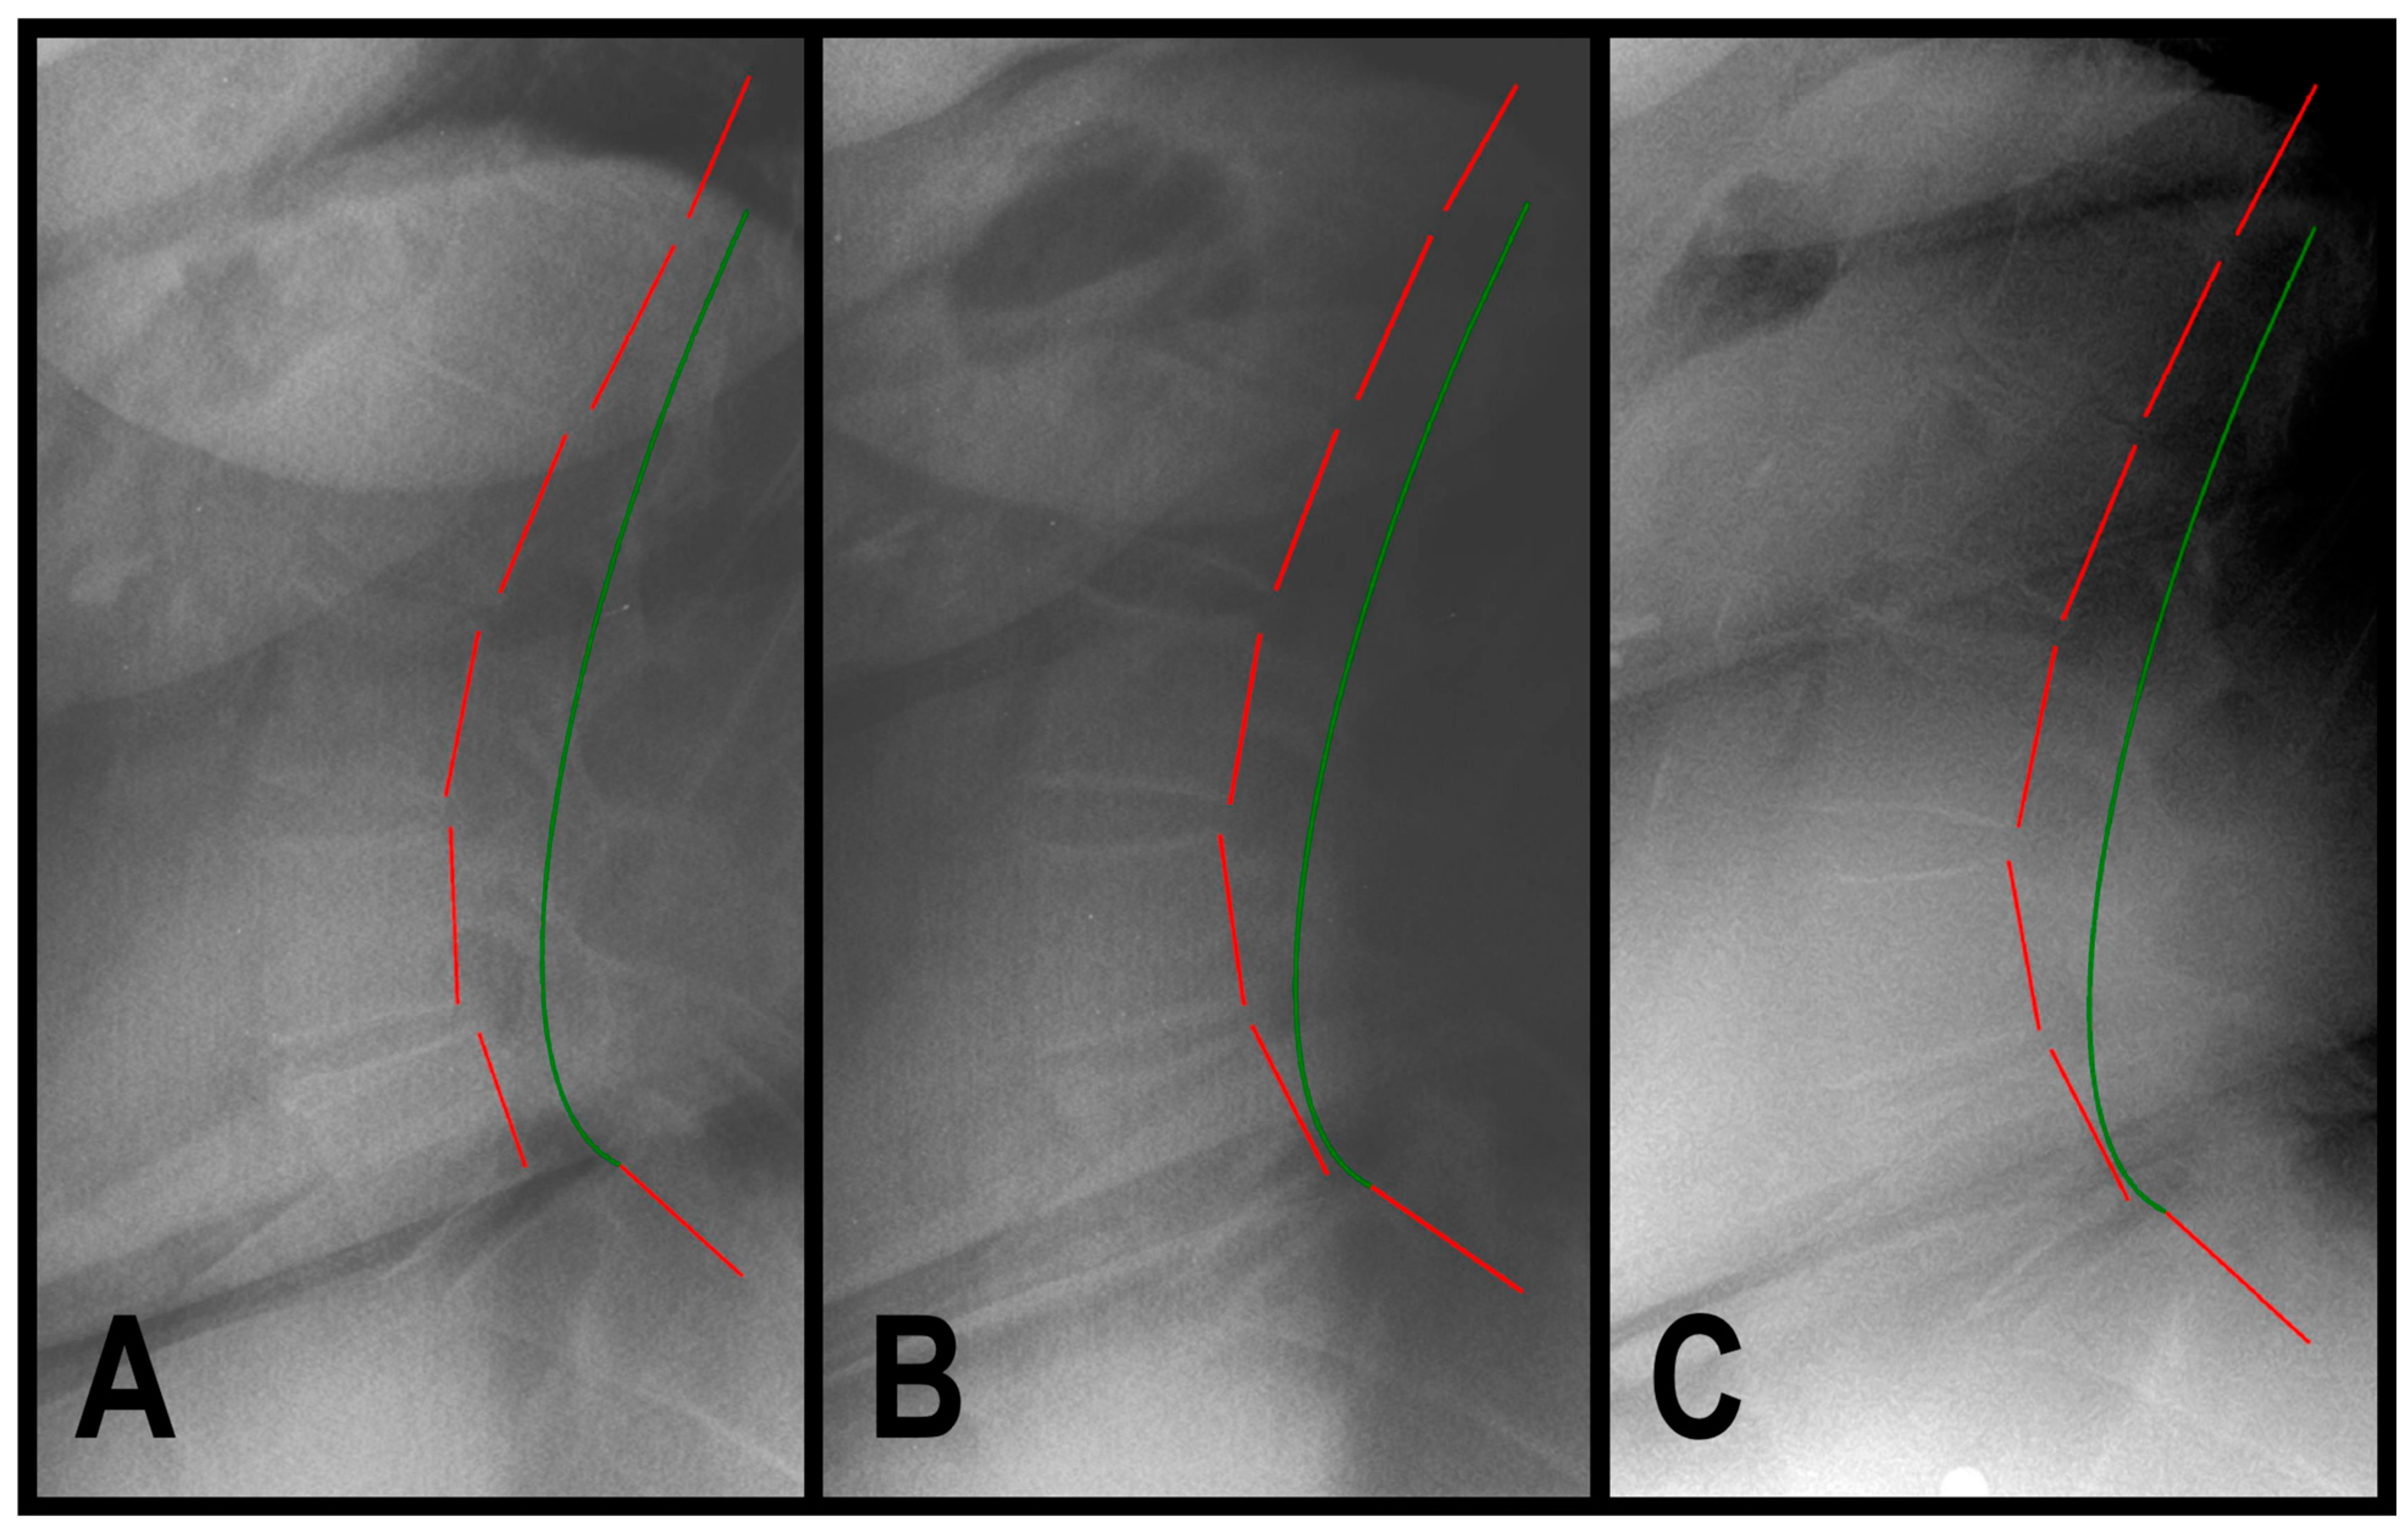

2.3. Radiographic Analysis

3.1.1. Patient 1

3.1.2. Patient 2

3.1.3. Patient 3

| Assessment | Normal Value | Pre-Treatment Exam 9/2019 | Post-Treatment Exam 12/2019 | 4-Year Follow-Up Exam 1/2024 | |

|---|---|---|---|---|---|

| Back Pain NRS | 0 | 7 | 1 | 2 | |

| SF-36 HRQOL Scales | PF | 72.0 | 45.0 | 85.0 | 80.0 |

| RP | 81.0 | 25.0 | 100.0 | 100.0 | |

| RE | 81.0 | 66.7 | 100.0 | 100.0 | |

| VT | 61.0 | 40.0 | 60.0 | 55.0 | |

| MH | 81.0 | 76.0 | 92.0 | 96.0 | |

| SF | 83.0 | 87.5 | 100.0 | 100.0 | |

| BP | 75.0 | 45.0 | 90.0 | 87.5 | |

| GH | 72.0 | 67.5 | 80.0 | 80.0 | |

| ΔH | 84.0 | 25.0 | 75.0 | 75.0 | |

| PCS | 46.8 | 32.6 | 51.7 | 49.9 | |

| MCS | 52.8 | 53.8 | 57.5 | 58.7 | |

| ARA L1-L5 (°) | −40 | −47.8 | −41.1 | −43.4 | |

| Tz L5-S1 (mm) | 0 | 15.8 | 4.2 | 4.3 | |

| Urination Frequency (times/24 h) | 0 | 6 | 6 | 6 | |

| Urinary Urgency NRS | 0 | 8 | 2 | 2 | |